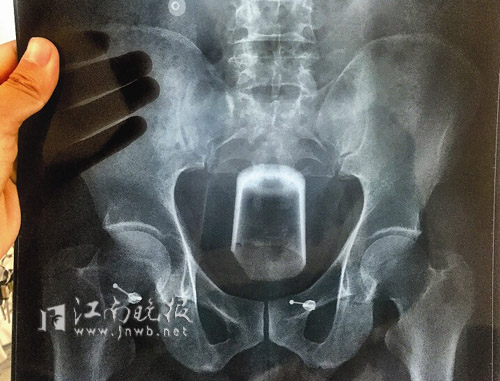

Ảnh chụp X-quang có chiếc cốc trong trực tràng người đàn ông. |

Khi bác sĩ Lý Xuân Vĩ, trưởng khoa Hậu môn trực tràng của bệnh viện xem phim X-quang cũng cảm thấy rất khó khăn. Trong trực tràng của người đàn ông này có một cốc thủy tinh rất lớn lại trơn khó nắm bắt. Mặt khác miệng cốc rộng, đáy cốc hẹp và miệng cốc lại hướng xuống dưới. Chưa kể trước đó người đàn ông này đã đến một bệnh viện khác để chữa và bác sĩ ở viện này đã làm hỏng chiếc cốc. Điều này có nghĩa là nếu chỉ một chút bất cẩn, cạnh sắc của cái cốc sẽ đâm thủng ruột khiến người này nguy hiểm tính mạng.